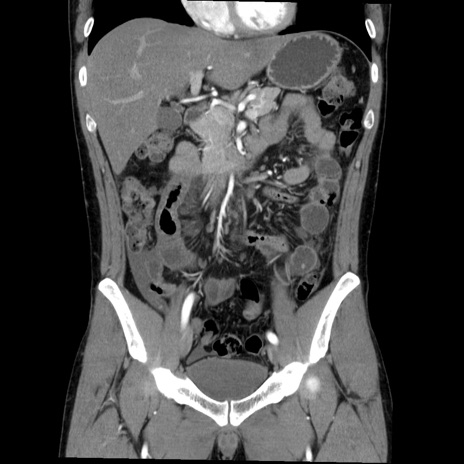

症例36(冠状断像)

【症例】20歳代 男性

【主訴】心窩部痛

【現病歴】今朝より上腹部痛あり。一旦軽快していたが再度出現したため救急要請。昨日夕に白身の魚を含む刺身を食べた。

【身体所見】BP 136/89mmHg、HR 74/min、BT 37.0℃、腹部:膨満、軟、心窩部に圧痛あり。反跳痛なし、筋性防御なし、腸雑音やや亢進あり。

【データ】WBC 17700、CRP 0.48